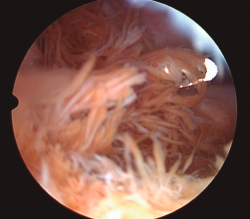

Figura 7. Resección de sinovitis villonodular pigmentada en la región posteromedial de la rodilla derecha. Visión transescotadura, uso de sinoviotomo por portal posteromedial.

Esta técnica no forma parte de los gestos habituales durante una artroscopia rutinaria de rodilla, pero resulta muy útil en cirugías como la resección de ciertos tumores (destacando por su frecuencia la sinovitis villonodular pigmentada) (Figura 7), el abordaje a la fabela (Figura 8), la extracción de cuerpos libres o el reanclaje de avulsiones óseas de la inserción tibial del LCP. Además, la creación de este portal permite una buena visualización de la porción posterosuperior de ambos cóndilos femorales y de la cara posterior del LCP, del ligamento de Wrisberg, del tendón poplíteo y de la unión meniscocapsular de ambos meniscos(24)(Figuras 9 y 10).